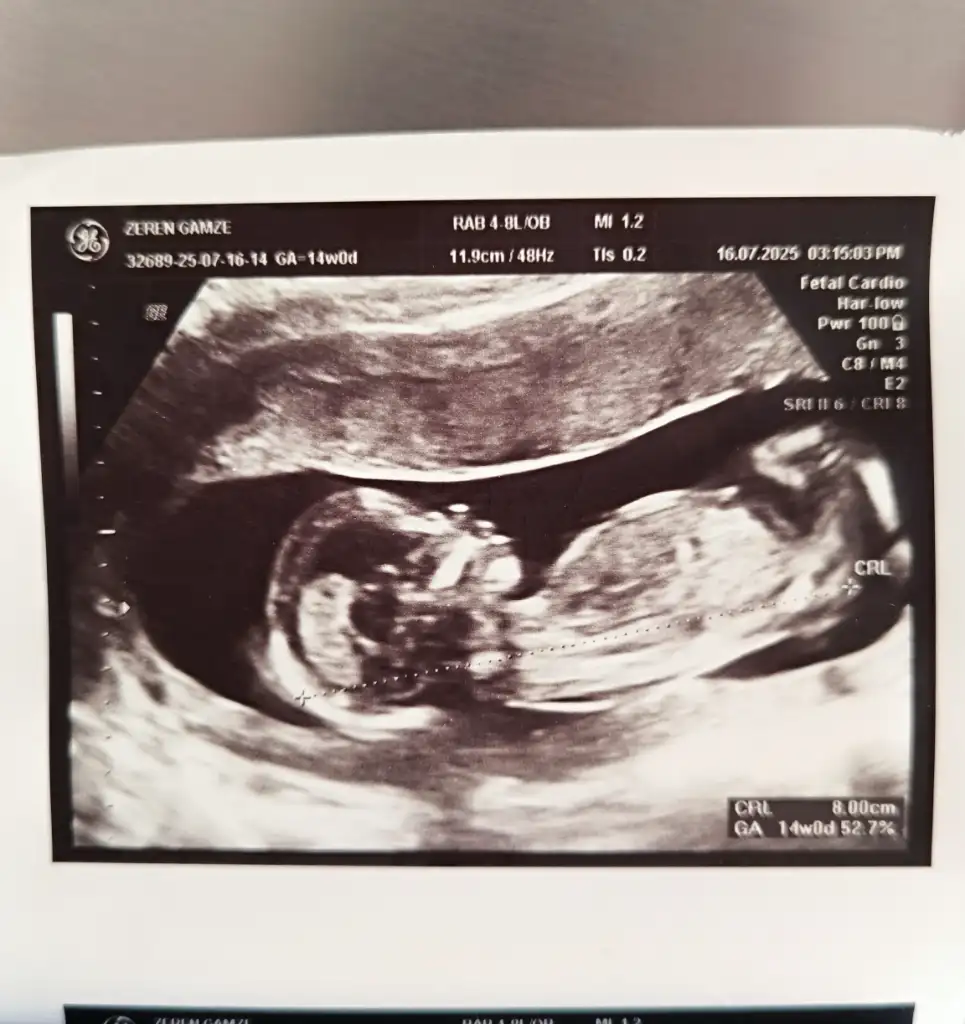

Hadi gözün aydın saglıklı olsunlarda biz senle aynıyız crl kaç çıktı gamze haftayla uyumlumuArkadaşlar bugün kontrolüm vardı, çok şükür her şey yolunda tam 14. Haftamdayım veeeee cinsiyeti öğrendikben hissetmiştim biliyordum zaten erkekmiş

Şöyle bırakayım görüntüyü o zamanHadi gözün aydın saglıklı olsunlarda biz senle aynıyız crl kaç çıktı gamze haftayla uyumlumu